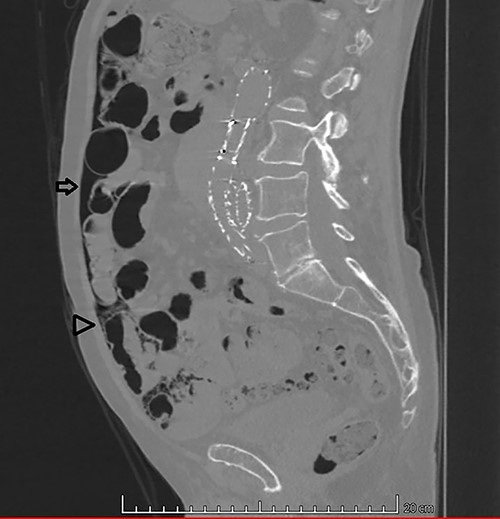

An 87-year-old male patient came to the radiology department to perform an abdominal computed tomography (CT) for follow-up of a bladder urothelial carcinoma. Upon CT evaluation, diffuse intestinal pneumatosis associated with pneumoperitoneum was identified on the exam (Fig. 1). The patient was called to return promptly to the hospital.

Sagittal CT image in lung window: (arrow) pneumoperitoneum and (arrow head) ‘bubbles’ within the walls of small intestine segment and the adjacent mesentery, featuring pneumatosis cystoides intestinalis and mesenteric.

He arrived at the emergency department walking and with no clinical distress. He was complaining of hematuria for a month and worsening of chronic constipation in the last 2 days. Physical examination demonstrated discrete abdominal distention. Laboratory tests showed normal c-reactive protein (CRP), white blood cell count and lactate level. A new CT revealed no change in the previous findings: intestinal pneumatosis and pneumoperitoneum (Figs 2 and 3).